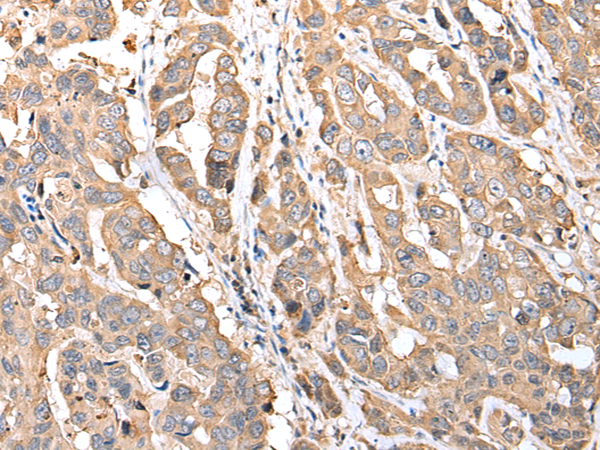

IHC positive control:

Human breast cancer

IHC Recommend dilution:

25-100